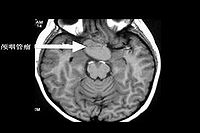

颅咽管瘤(craniopharyngioma)起源于垂体胚胎发生过程中残存的扁平上皮细胞,是一种常见的先天性颅内良性肿瘤,大多位于蝶鞍之上,少数在鞍内。颅咽管瘤的异名很多,与起始部位和生长有关,如鞍上囊肿、颅颊囊肿瘤、垂体管肿瘤、造釉细胞瘤上皮囊肿、釉质瘤等。颅咽管瘤起病多在儿童及青少年。其主要临床特点有下丘脑-垂体功能紊乱颅内压增高视力视野障碍、尿崩症以及神经和精神症状。CT扫描可明确诊断。治疗主要为手术切除肿瘤。

2.CT扫描颅脑CT扫描显示为鞍区肿瘤改变,非增强扫描者实质性肿瘤表现为高密度或等密度影像,钙化斑为高密度,囊性者因瘤内含胆固醇而呈低密度像,CT值为-40~10Hu,囊壁为等密度。病变边界清楚,呈圆形、卵圆形或分叶状,两侧侧脑室司扩大。强化扫描时约2/3的病例可有不同程度的增强,CT值增加12~14Hu,囊性颅咽管瘤呈环状强化或多环状强化而中心低密度区无强化,少数颅咽管瘤不强化。一般具有钙化、囊腔及强化后增强三项表现的鞍区肿瘤。